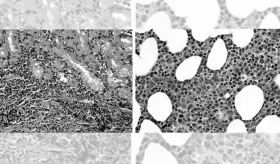

Es un tipo de cáncer que inicia en el tejido de formación de la sangre como la médula ósea y provoca un gran numero de celulas sanguineas anormales entre en el torrente sanguíneo.

Nuevo subtipo de leucemia mostraría aumento en la cantidad de proteínas mitocondriales, y alteraciones en el metabolismo mitocondrial